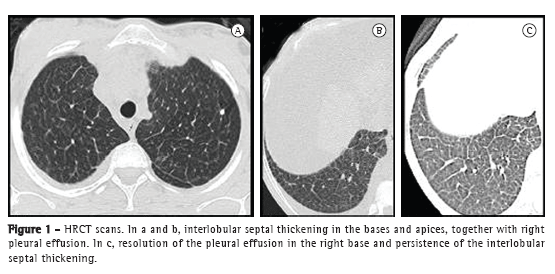

Niemann-Pick disease (NPD) is a rare lysosomal storage disorder that is generalized and severe, as well as being characterized by intracellular sphingomyelin accumulation caused by deficiency of sphingomyelinase activity.(1) From a respiratory standpoint, the various types of NPD, including type B, can cause progressive loss of pulmonary function, with suggestive radiological findings. We report the case of a 27-year-old female patient with type B NPD. The patient was initially referred for outpatient treatment in 2003, presenting with a history of hepatosplenomegaly and delayed psychomotor development since childhood. The diagnosis of NPD was confirmed by measuring peripheral leukocyte sphingomyelinase activity, which was found to be decreased (0.009 nmol  h−1  mg−1 of protein; reference value, 0.745 nmol  h−1  mg−1 of protein). Serology for HIV, hepatitis B, and hepatitis C was negative, as was serology for syphilis (venereal disease research laboratory test). In addition, ANF was negative. Gaucher's disease was ruled out because beta-glucosidase levels were normal. The patient developed ascites and complained of mild dyspnea, being referred to the pulmonology clinic. She underwent a six-minute walk test (six-minute walk distance [6MWD] = 396 m; predicted 6MWD = 724 m), showing intense dyspnea at the end of the test (modified Borg scale score = 9) but no oxygen desaturation (SpO2 = 97%). Spirometry results were suggestive of restrictive lung disease (FEV1 = 1.77 L [61% of predicted]; FVC = 2.07 L [57% of predicted]; and FEV1/FVC ratio = 85%). A chest X-ray revealed no pulmonary changes. An HRCT scan revealed interlobular septal thickening in the bases and apices, together with right pleural effusion (Figures 1a and 1b).

The patient developed chronic liver failure, having undergone orthotopic liver transplantation with splenectomy in September 2010. Four months later, there was complete resolution of the respiratory symptoms. At the time, a second pulmonary function test revealed improvement in the spirometric parameters (FEV1 = 2.53 L [80.7% of predicted]; FVC = 2.79 L [77.8% of predicted]; and FEV1/FVC ratio = 90.8%), and there was improvement in the 6MWD, which increased to 426 m, without desaturation (SpO2 = 98%). A second HRCT scan revealed resolution of the pleural effusion (Figure 1c) and persistence of the interlobular septal thickening.

The literature contains few reports of type B NPD patients submitted to liver transplantation, and little is known about the course of the disease after the procedure.(3) In this case report, the patient was asymptomatic after surgery, and it is likely that the respiratory complaints and the initial spirometric findings were related to liver involvement (pleural effusion, ascites, and pancytopenia due to hypersplenism). The CT findings obtained after liver transplantation revealed resolution of the pleural effusion and persistence of the interlobular septal thickening. The six-minute walk test was performed without continuous SpO2 recording, which could be more appropriate for a better analysis of the patient response to stress, and the diffusing capacity of the lung for carbon monoxide was not measured.(8)